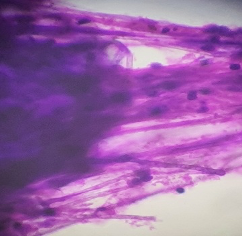

A 52 year old male was clinically diagnosed with a space-occupying lesion in the left parietal lobe of brain. Squash and other smears were made .3 images are shown, make you diagnosis and why?